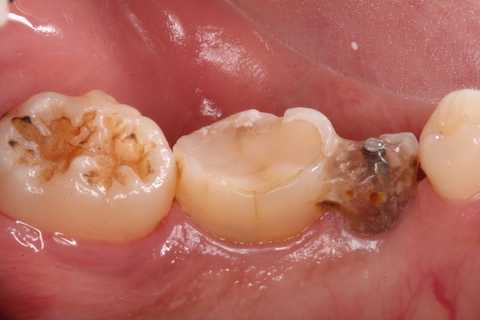

今日の抜歯再植術シリーズ39.3 2025.11.16

今日の抜歯再植術シリーズ39.2 2025.11.15